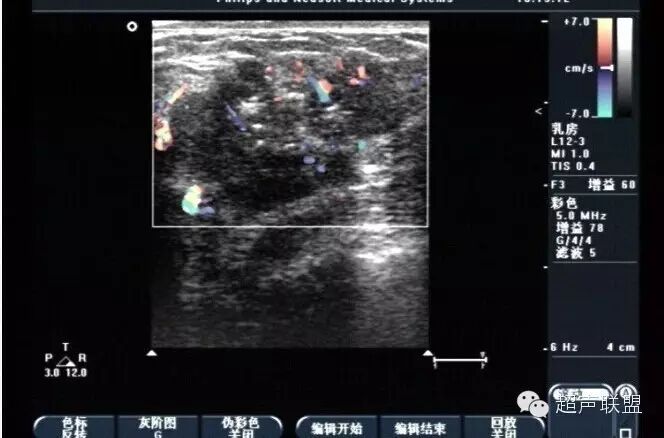

谐波成像是利用探头超声波的二次谐波成像。该技术可有效地抑制超声混响效应及其它近场噪声,但可能会限制穿透深度而导致分辨率下降,除非运用更新的宽带谐波成像技术。如图3所示液态肿块的内部回声在谐波影像中有所下降。

谐波成像减少了通常乳腺超声中可能出现的复杂液态和固态肿块的数目,同时提高了鉴定肿块为固态还是液态的准确性。该项技术也可能更清晰地定义病变边界——一个区分良性和恶性的重要特征。